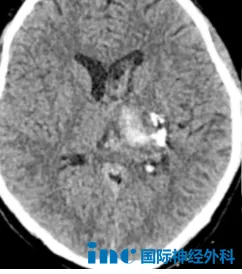

2021年,22岁的阿豪因持续头晕、乏力、呕吐就医。本以为是寻常小疾,却没想到问题竟出在“生命中枢”——脑干。影像检查显示,延髓海绵状血管瘤。

2023年3月29日,在国内神经外科团队的密切配合下,巴教授主刀,成功为他全切了脑干海绵状血管瘤。

复查影像显示:肿瘤无残留、无复发,亦未出现任何新的神经功能损伤。教授建议,下一次复查可在2年后进行。